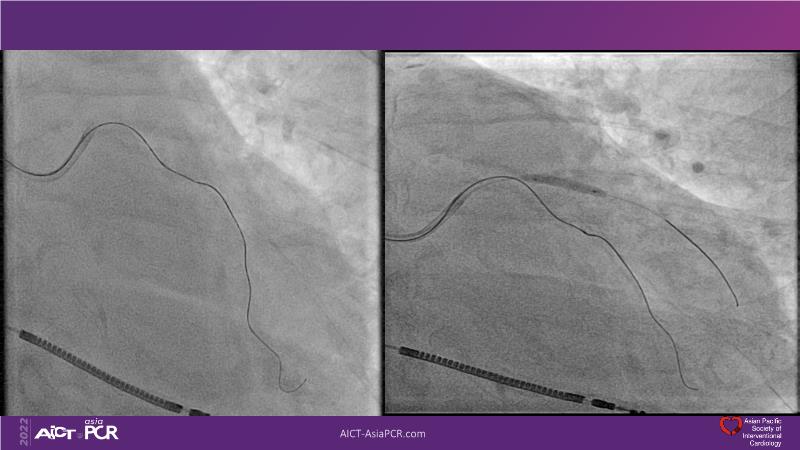

Cracking calcium: best practices to integrate intravascular lithotripsy into your calcium management algorithm

With this session, keep up to date on the evidence, trials and outcome data for intravascular lithotripsy in severely calcified lesions. Learn how to use this technique in real-world patients and understand its role in the treatment algorithm for severely calcified coronary lesions.

- To learn how to use intravascular lithotripsy in real-world patients with severely calcified coronary lesions